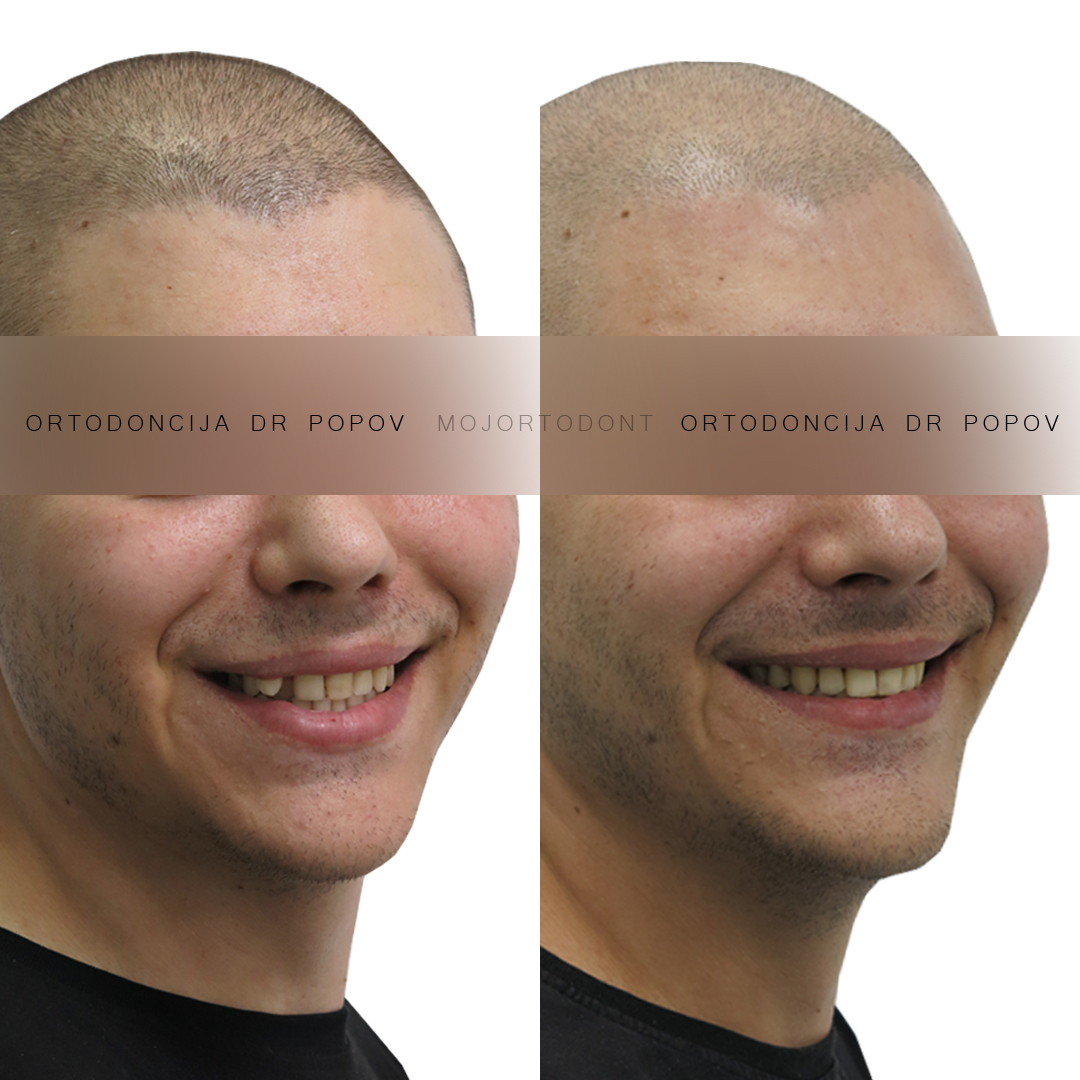

Uspešno završen slučaj ektopičnog očnjaka!

Kroz precizno planiran i stručno vođen ortodontski tretman, uspeli smo da rešimo sve ove probleme.

Ektopični očnjak je uspečno postavljen na svoje mesto, teskoba je otklonjena, a sredine zubnih nizova su dovedene u savršen sklad.

Zadovoljstvo nam je što smo mogli da pomognemo pacijentu da povrati pravilan zagrižaj i lep, simetričan osmeh. Posle perioda stabilizacije sledi izbeljivanje zuba i korekcija oblika estetskim restauracijama.